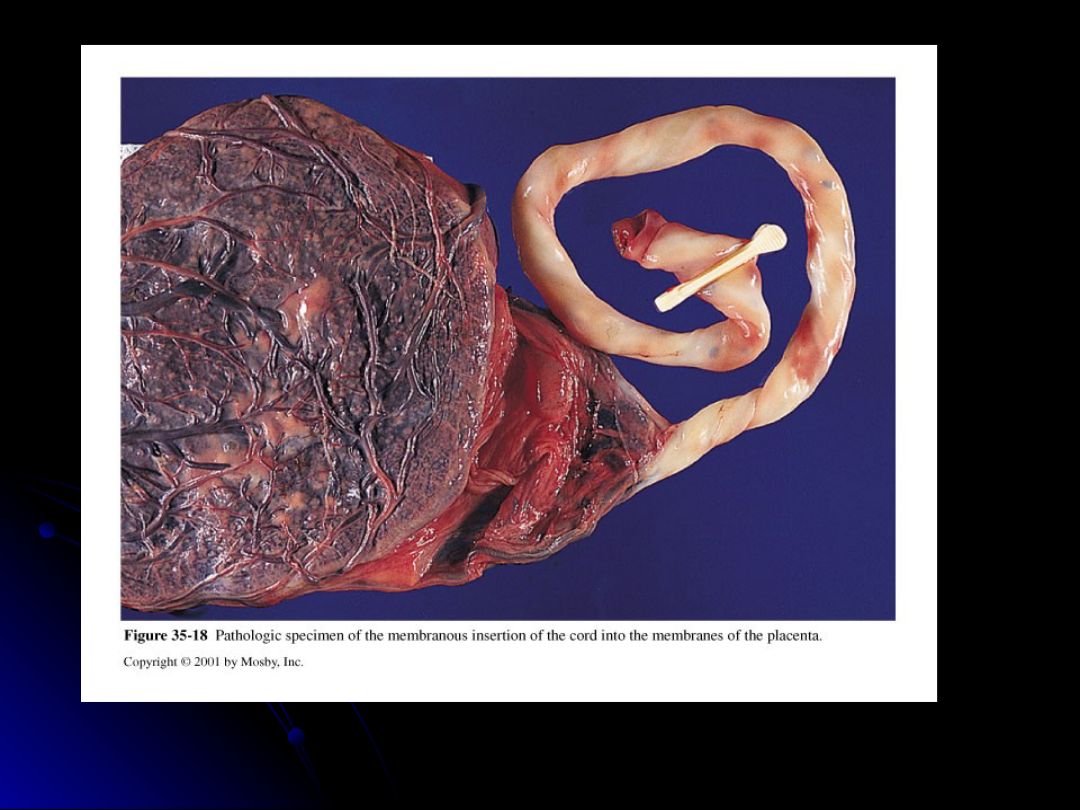

Which one of the following occurs when the cord inserts into the membranes before it enters the placenta?

velamentous insertion